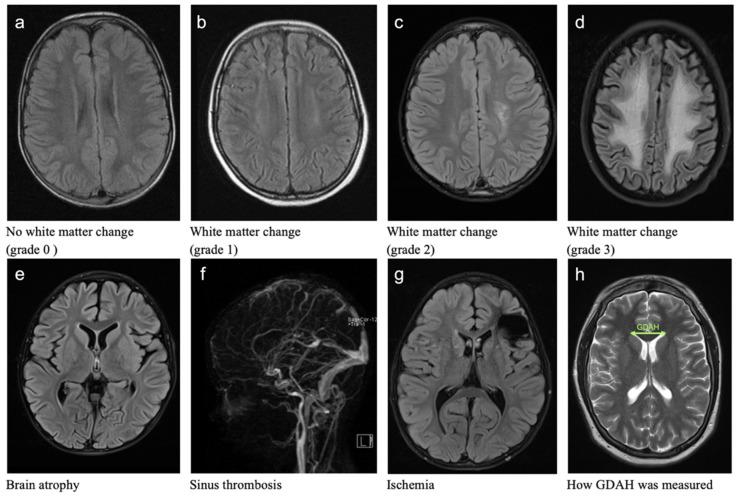

Due to high survival rates, long-term sequelae, especially neurotoxicity, need to be considered in childhood acute leukemias. In this retrospective analysis of morphologic changes of the brain in children treated for acute leukemias, we included 94 patients (77 ALL, 17 AML; 51 male, 43 female; median age: 5 years) from a single center. We analyzed 170 cranial MRI scans (T2, FLAIR axial) for morphologic alterations of the brain and variations of the ventricular width (GDAH). In addition, the corresponding literature was reviewed. More than 50% of all patients showed cerebral pathomorphologies (CP). They were seen more often in children with ALL (55.8%), ≤ 6 years of age (60.8%), in relapse (58.8%) or after CNS irradiation (75.0%) and included white matter changes, brain atrophy, sinus vein thrombosis and ischemic events. GDAH significantly enlarged mainly in children up to 6 years, with relapse, high-risk leukemias or ALL patients. However, GDAH can normalize again. The number of intrathecal Methotrexate applications (≤12 vs. >12) showed no correlation to morphologic alterations besides a significant increase in GDAH (−0.3 vs. 0.9 mm) between the first and last follow-up MRI in ALL patients receiving >12 ith. MTX applications. The role of ith. MTX on CP needs to be further investigated and correlated to the neurocognitive outcome of children with acute leukemias.